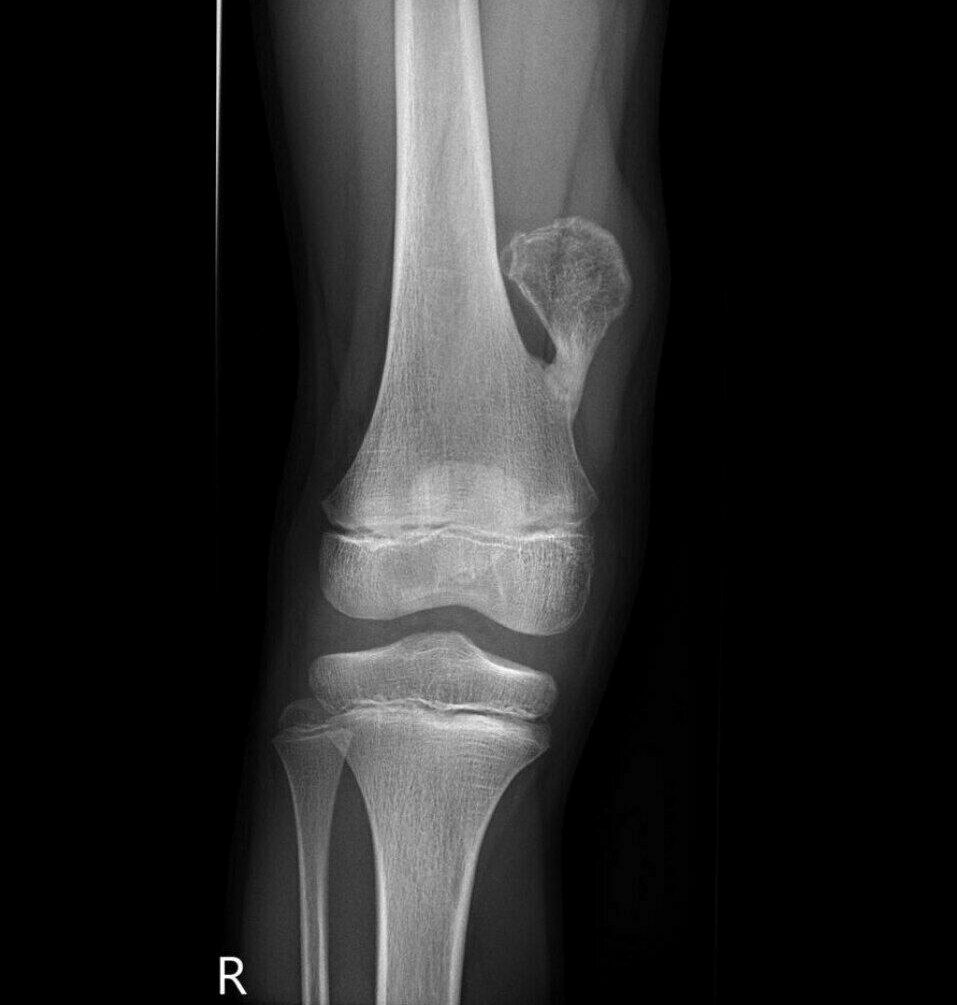

Distal femoral osteochondroma

Osteochondroma